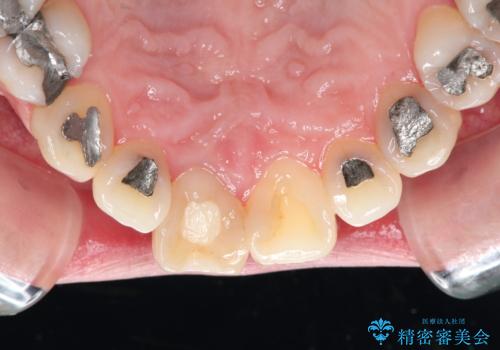

- 前歯の変色が主訴で来院した患者様です。

お痛みは無く、たまに異和感があるとのことでレントゲン撮影をすると、以前根の治療をされた際の器具が破折したまま残っていました。

破折した器具を除去したのち、根管治療、ファイバーコア築造、セラミッククラウンの製作を行いました。